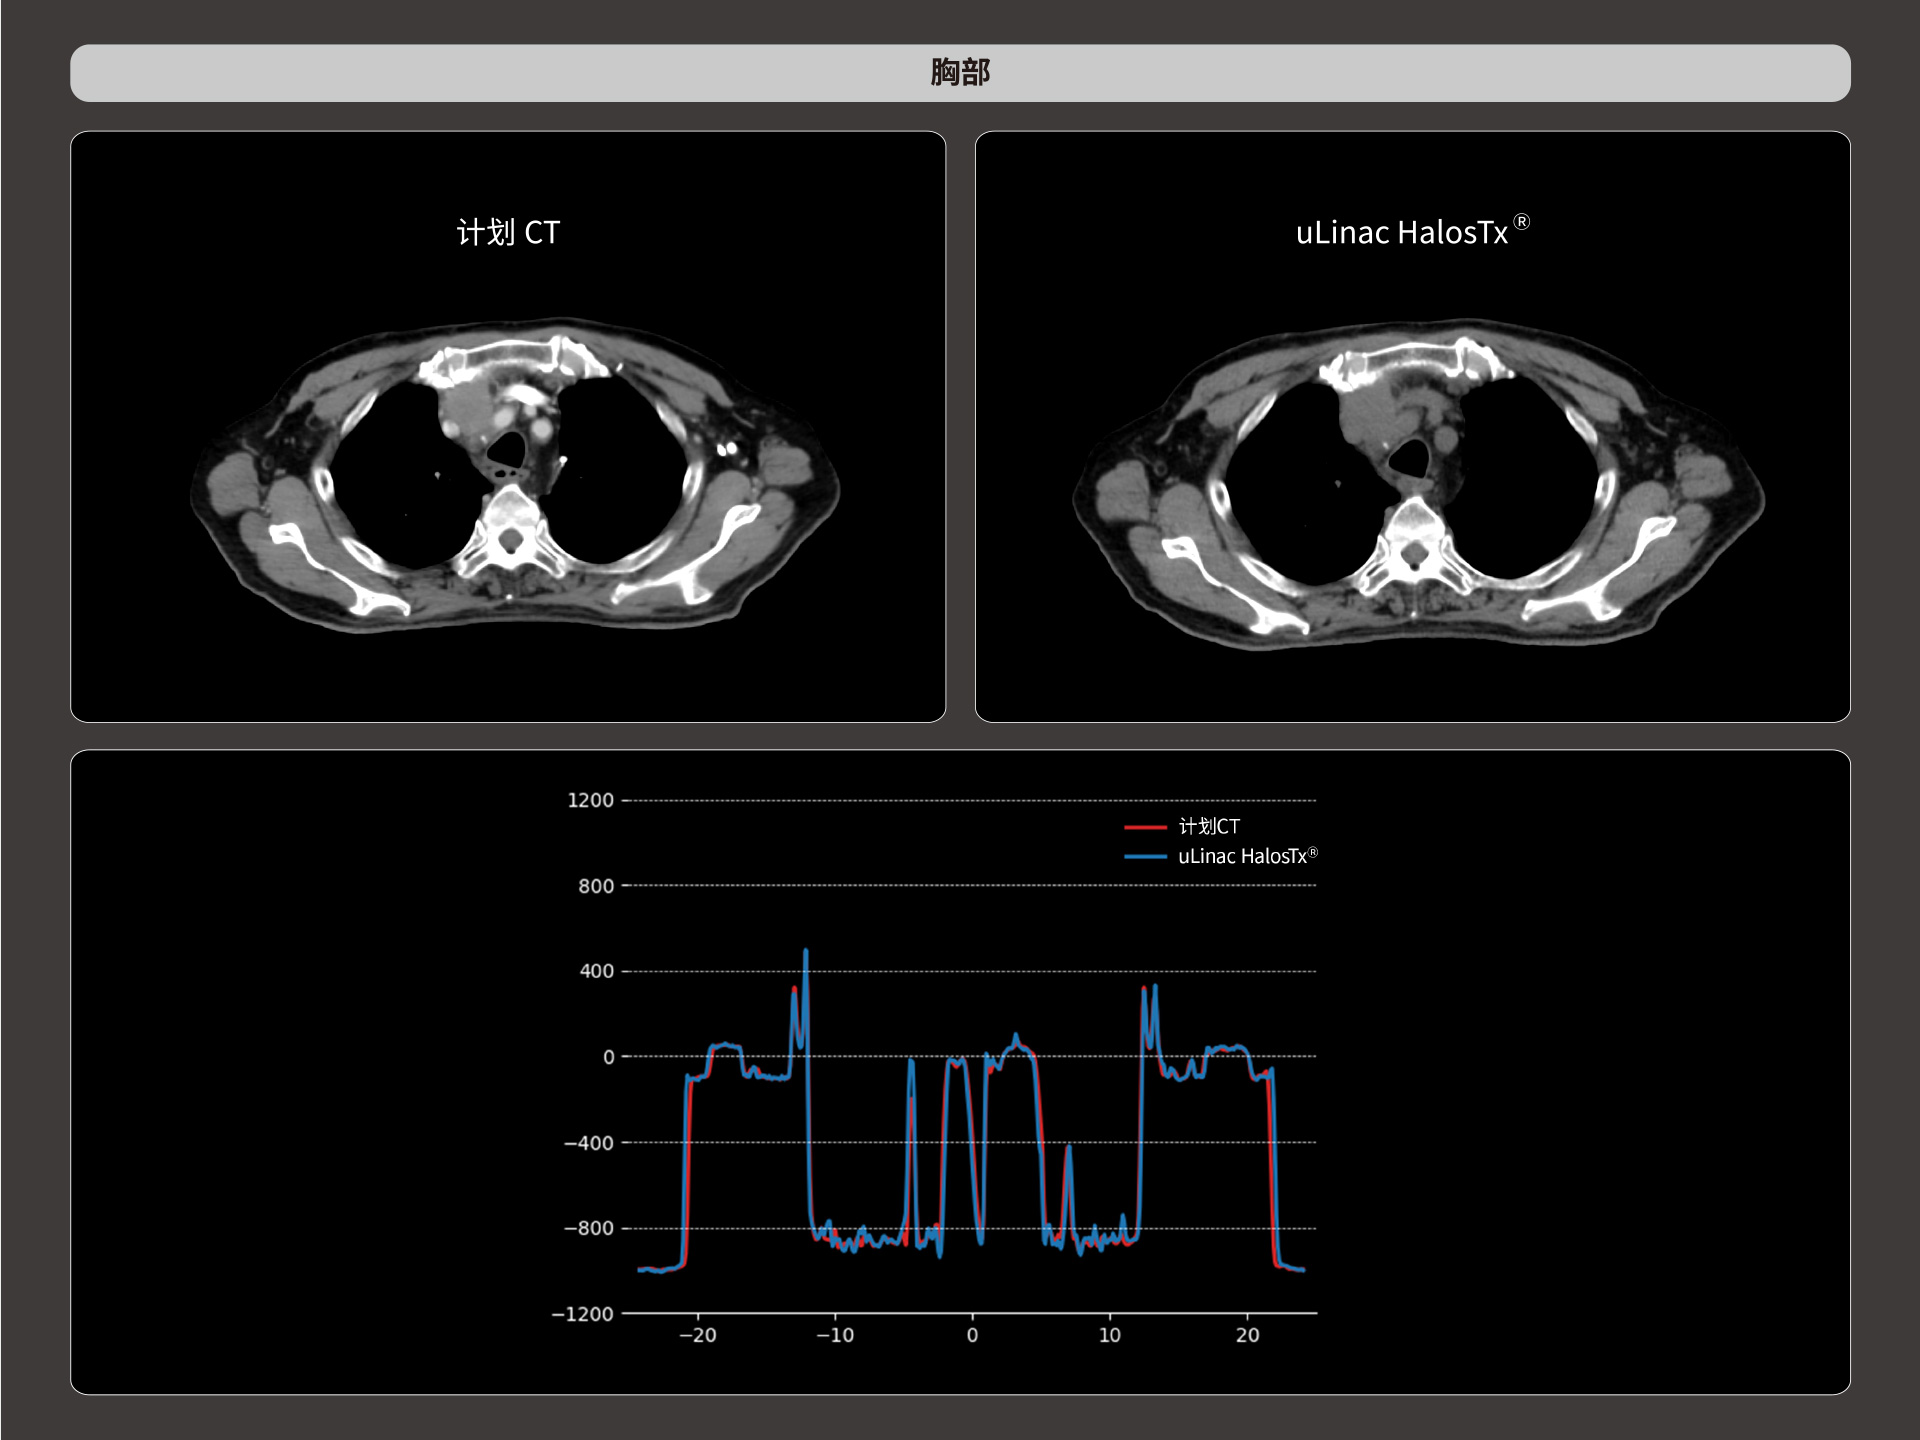

精准CT值,完美满足勾画、剂量计算要求

提供传统 的CT 模拟机所一致的HU值精度(±10HU)

HU金标准

从数据源头提升图像质量,高清呈现细微变化,全面精进机载影像实力